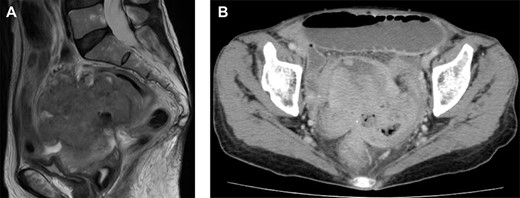

Magnetic resonance imaging and computed tomography (CT) findings preoperatively. (A) Sagittal T2-weighted MRI scan demonstrating a pelvic mass involving the uterus and rectum. (B) CT scan showing expansion of the intestines and the absence of free intraperitoneal air.

the uterus and rectum (Fig. 2A). The computed tomography scan showed expansion of the intestines and no evidence of free intraperitoneal air (Fig. 2B). As she had a history of bloody stool and the CEA level was increased, we performed colonoscopy, which showed a malignant tumor of the rectum (Fig. 3). The protruding tumor was located 7 cm from the anus. Exploratory laparotomy showed a 90-mm pelvic mass involving the uterus, ileum and rectum. Therefore, we performed an en bloc resection of the mass, including total hysterectomy, bilateral salpingo-oophorectomy, partial resection of the ileum and the Hartmann operation. Macroscopically, the resected pelvic mass invaded the uterus, intestine and rectum, and a colouterine fistula was identified (Fig. 4). The main portion of the tumor was located in the rectum, and it grossly appeared that tumor invasion occurred from the rectum to the uterus and ileum. Microscopic examination of the pelvic mass showed complicated glandular structures in a desmoplastic stroma. The cells forming the lumen were primarily columnar epithelium, consistency of the small glandular cavity was high and severe dyskaryotic cells were multilayered. The nuclei were enlarged and irregularly shaped, contained coarse chromatin and showed atypia. Immunohistochemical staining was performed. Cytokeratin (CK)20 (Dako), NCL-Villin (Novocastra) and CEA (Dako) were positive, and CK7 (Dako) was negative. The final diagnosis was moderately differentiated tubular adenocarcinoma of the rectum, stage IIC, pT4b N0 M0. The patient’s postoperative course was uneventful. The serum level of CEA returned within normal range 1 month postoperatively. Adjuvant chemotherapy (TS-1) was administered for 6 months postoperatively. The patient has been followed up with for >12 months without any signs of recurrence.